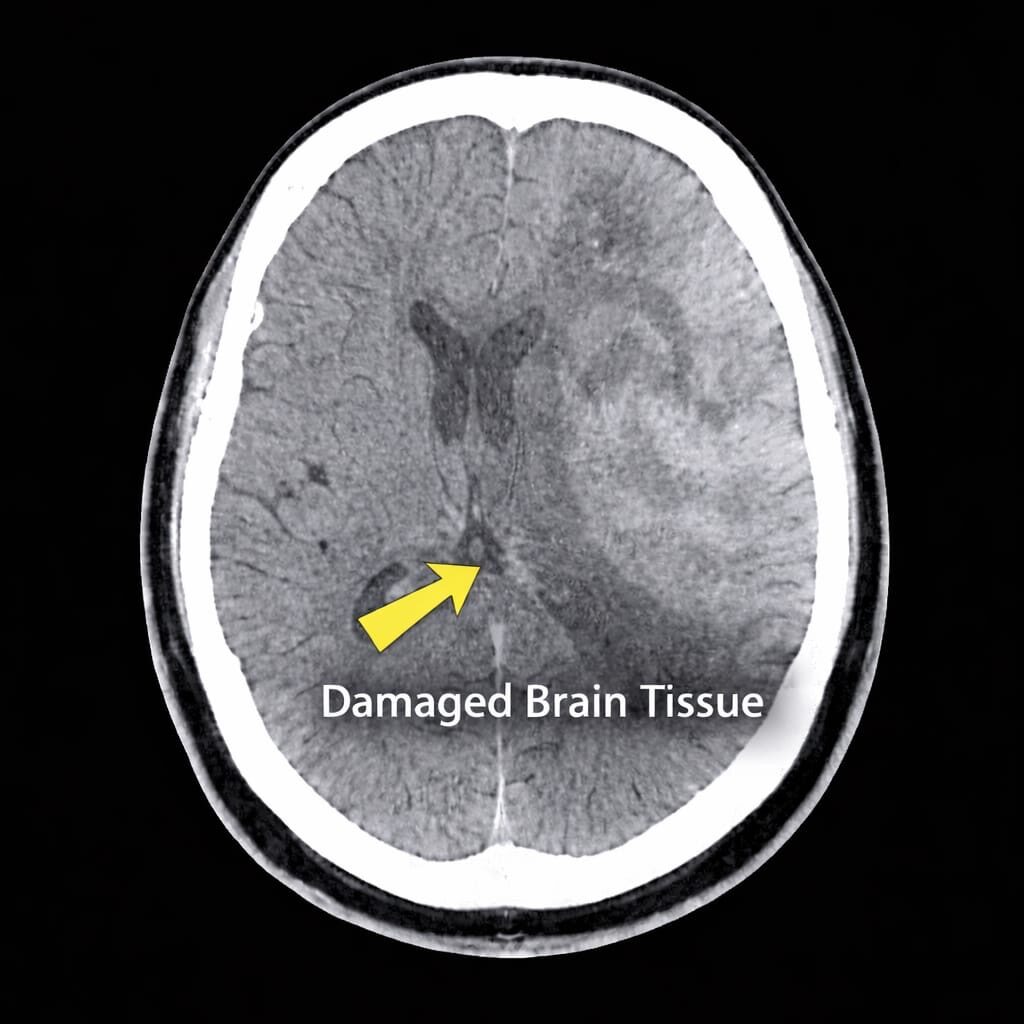

A stroke, in easy words, basically refers to when a part of the brain suddenly loses blood supply. The brain, as any other organ, requires a constant supply of oxygen and nutrients. When the blood flow is interrupted, the brain cells begin to die in minutes, causing a stroke.

1. Ischemic stroke

Caused by a block in the blood vessel that prevents blood from reaching a specific part of the brain.

2. Hemorrhagic stroke

Caused by bleeding in or around the brain due to a ruptured vessel in the brain.

This is a classic case of Acute ischemic stroke with the distal left internal carotid artery occlusion.

The family assumed it was fatigue and decided to “wait and see”. He reached the hospital six hours later. By then, significant brain damage had already occurred.